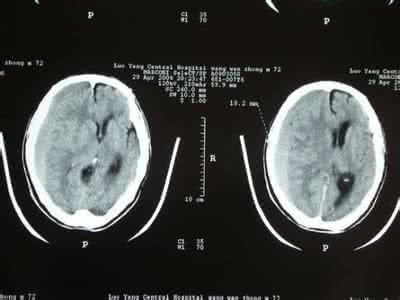

一、适应征:1、诊断性穿刺(1)、脑室造影;(2)、采集脑脊液标本作化验;(3)、鉴别脑积水的类型。即作脑室和腰椎双室穿刺,用染料测试两者是否相通。方法:将染料(对神经组织无损伤)如PSP与靛胭脂注入侧脑室内,如果染料能出现在腰椎穿刺的CS

(一)一般检查1.意识和精神行为状态可根据小儿对各种刺激的反应来判断意识水平(即意识深、浅度)有无障碍,由轻而重分为嗜睡、昏睡、半昏迷和昏迷等。少数主要表现为谵妄、定向力丧失和精神行为异常等意识内容的减少或异常。智力低下者